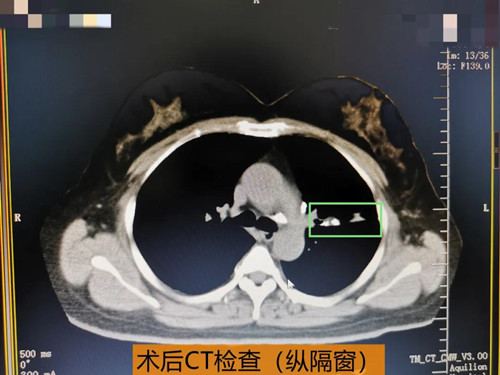

起初王女士对支气管镜检查有些抵触、担忧,为了消除王女士的焦虑、恐惧情绪,张主任详细讲解了支气管镜检查对于疾病诊治的必要性,并建议王女士可以选择无痛支气管镜检查以减少检查过程中的不适。消除了顾虑的王女士来到呼吸内科接受了支气管镜检查,支气管镜下的影像也让医生们大吃一惊,原来阻塞王女士左肺上叶支气管的不是肿瘤,也不是痰栓,而是像被腐蚀的牙齿一样坚硬的异物,术前了解到王女士并没有异物吸入史,看来这块异物应该是生长在支气管里的,张主任在仔细探查及判断异物形态及与周围组织的关系后,果断决定在进行气管镜检查的同时,将该异物通过气管镜取出,并行病理检查,果然取出的异物病理提示是钙盐沉积,也就是说这是一颗长在支气管里的结石。取出支气管结石后,王女士呼吸顺畅,可自主咳痰,心慌、气短症状明显改善,经抗感染治疗后,胸痛症状缓解。之前的症状都是这块结石惹的祸,病因查明,问题解决,结石取出,困扰王女士许久的心里“石头”终于落地了。